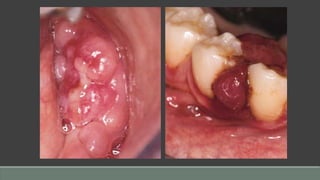

Pyogenic Granuloma

Clinical Presentation

• Occurs at any age, but usually in children, young adults, and women

• Red, lobular to smoothly contoured appearance

• When ulcerated, a yellow fibrinous exudate covers the lesion.

• Sessile to pedunculated commonly on gingiva, but also on areas that are traumatized (eg,

lower lip, buccal mucosa)

• Bleeds easily but is painless